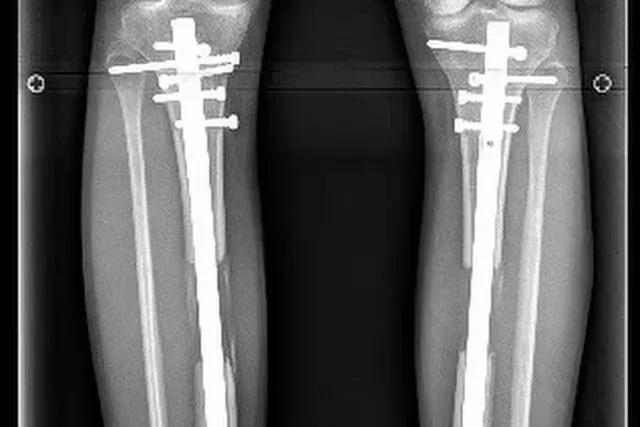

กระบวนการนี้ไม่ใช่เรื่องเล็ก แพทย์ต้องทำการผ่าตัดกระดูก และใช้เครื่องมือภายในเพื่อค่อยๆ ยืดระยะกระดูกออกทีละเล็กน้อยในแต่ละวัน โดยทั่วไปอาจอยู่ที่ประมาณ 1 มิลลิเมตรต่อวัน เพื่อให้ร่างกายสร้างเนื้อเยื่อใหม่เติมช่องว่าง

เทเรเซียเข้ารับการผ่าตัดมากกว่า 1 ครั้งตลอดหลายปี จนสุดท้ายมีส่วนสูงประมาณ 184 เซนติเมตร และช่วงขาที่ยาวขึ้นอย่างเห็นได้ชัด แต่เธอก็ต้องเผชิญกับภาวะแทรกซ้อน เช่น การติดเชื้อ และปัญหาในการเคลื่อนไหวในบางช่วง

ในเวลาต่อมา เธอตัดสินใจเข้ารับการผ่าตัดเพื่อนำอุปกรณ์โลหะออกจากร่างกาย ซึ่งเธอเรียกมันว่า “การปลดปล่อย” จากอดีตที่เคยยึดโยงตัวเธอไว้